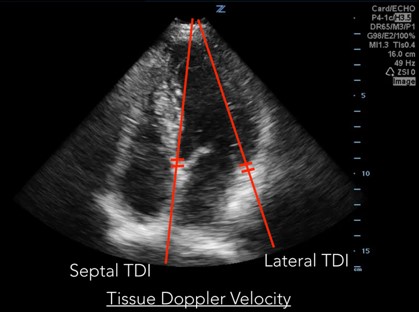

Measurements of diastolic function are obtained using Spectral Doppler to measure blood and tissue velocities. Pulsed wave Doppler uses the Doppler effect to allow assessment of both blood and tissue velocity and direction. The sample gate of the pulsed wave Doppler is placed between the tips of the mitral valve leaflets to measure blood velocity. (Figure 1) In addition to pulsed wave Doppler, tissue Doppler imaging setting is used to measure tissue velocity, and to determine the compliance of LV tissue during diastole. Tissue Doppler imaging filters out higher velocity signals to improve imaging of lower tissue velocities. With Tissue Doppler, the sample gate is placed in either of two locations: at the septal mitral annulus or at the lateral mitral annulus. (Figure 2) All measurements are performed on the apical four chamber view.

Fig 2. Tissue Doppler Velocity